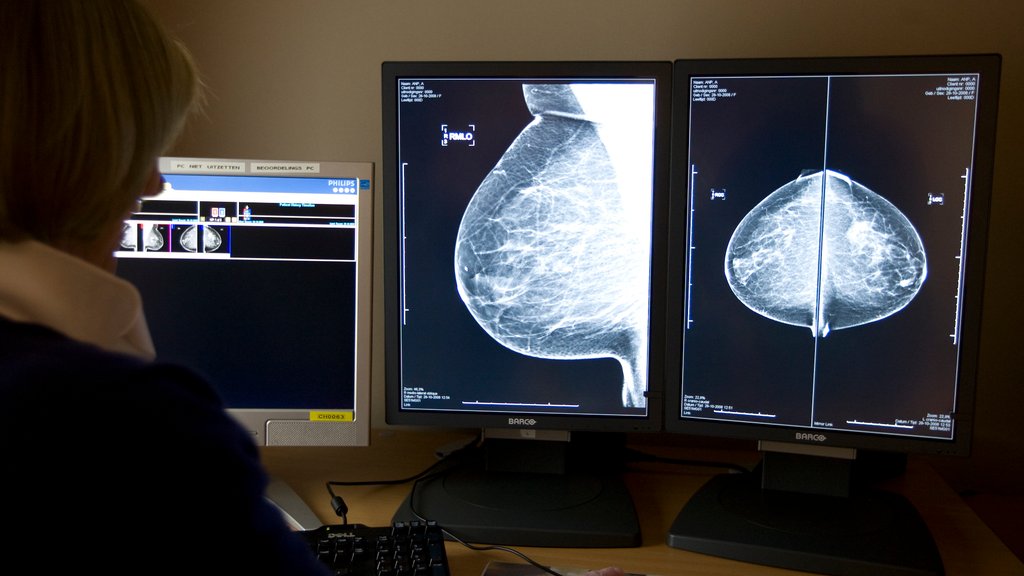

Opvallend in de cijfers is vooral de daling in het aantal gevallen van huidkanker, met gemiddeld 40 procent en de laatste twee weken zelfs met 50 procent. Bij borstkanker is die daling zo'n 28 procent.

De daling lijkt te worden veroorzaakt doordat mensen met klachten minder snel naar de huisarts gaan of minder snel worden doorverwezen naar het ziekenhuis. Ook zijn bevolkingsonderzoeken naar baarmoederhalskanker, borstkanker en darmkanker in maart stopgezet.